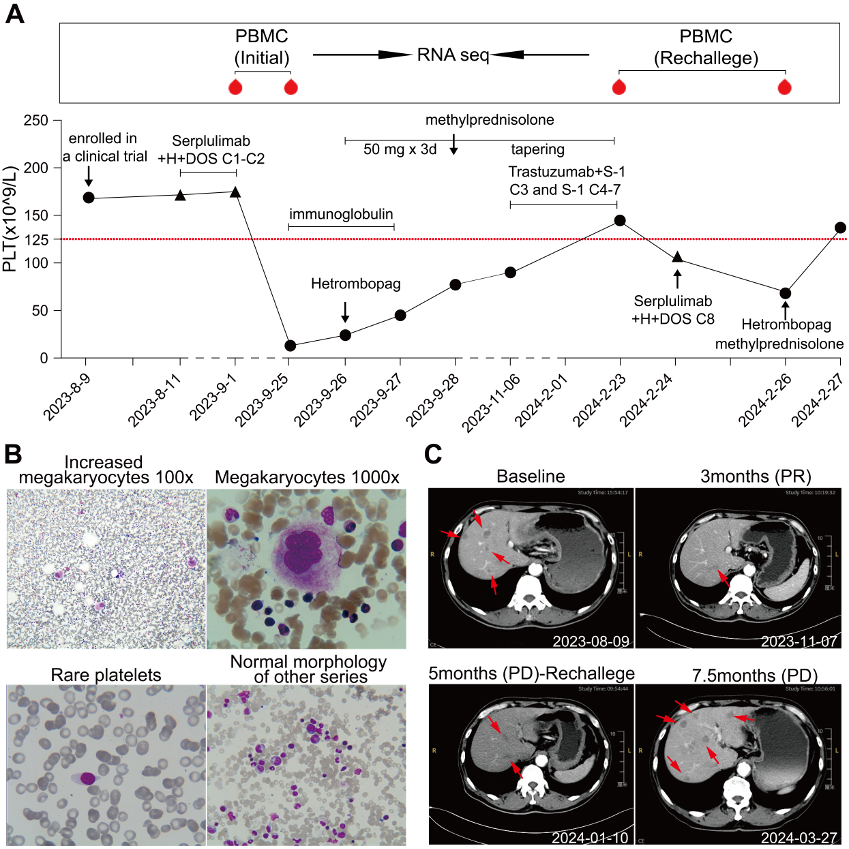

2023年,一例晚期胃腺癌(HER2阳性,PD-L1 CPS=10)患者加入一项临床研究,开始接受PD-1抑制剂斯鲁利单抗联合曲妥珠单抗及化疗(DOS方案)的一线治疗。然而在第二周期治疗后,患者出现了4级血小板减少(13×109/L)。经系统检查,确诊为免疫治疗相关的ITP。通过联合使用糖皮质激素、静脉注射免疫球蛋白及促血小板生成药物,患者血小板计数逐步回升。

尽管肿瘤达到部分缓解,但由于血小板恢复缓慢,后续治疗中暂停了PD-1抑制剂,仅采用维持治疗方案。至2024年初,血小板计数恢复正常,激素治疗也随之停止。

同年年初,因肿瘤出现进展,治疗团队决定再次启用PD-1抑制剂。但用药仅三天后,血小板水平便急剧下降,ITP复发。鉴于这一情况,最终决定永久停用该药物。

这项研究的重要突破,在于对患者的样本进行了全程动态追踪——在患者两次出现血小板减少的发病前后,都采集了外周血相关细胞进行专业的基因测序分析,通过对比找到了发病时稳定的分子表达变化规律。

一方面,检测发现有95个基因的表达显著升高,这些基因主要和T、B免疫细胞激活、抗原呈递、炎症反应等过程相关,意味着PD-1抑制剂可能打破了身体正常的免疫平衡,让免疫系统错误攻击自身血小板,导致血小板被异常清除。

另一方面,有231个基因的表达明显降低,这些基因集中在造血调控、干细胞分化等关键通路,说明在血小板被加速清除的同时,骨髓中负责生成血小板的巨核细胞,其分化和生成血小板的功能也受到了抑制。

同时,骨髓的相关检测结果也验证了这一发现:骨髓中参与免疫反应的相关细胞比例增高,和外周的免疫异常激活相呼应;而骨髓造血细胞的分化出现阻滞,也和造血相关基因活性降低的结果一致。